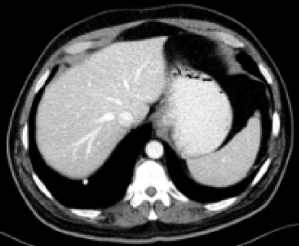

| LDCT (0.7586) | FDCT |

RED-CNN (0.8790)

| RED-CNN+SSWL (0.8901) | RVAE (0.8851) | RVAE+SSWL (0.9023) |

Figs. 3 and 4 demonstrate precise removal of noise from whole scans as well as specific regions of interest (ROIs), proving the effectiveness of our model over baseline architectures and other self-supervised tasks. As shown, both the RVAE and SSWL are able to quantitatively and qualitatively outperform their respective counterparts.